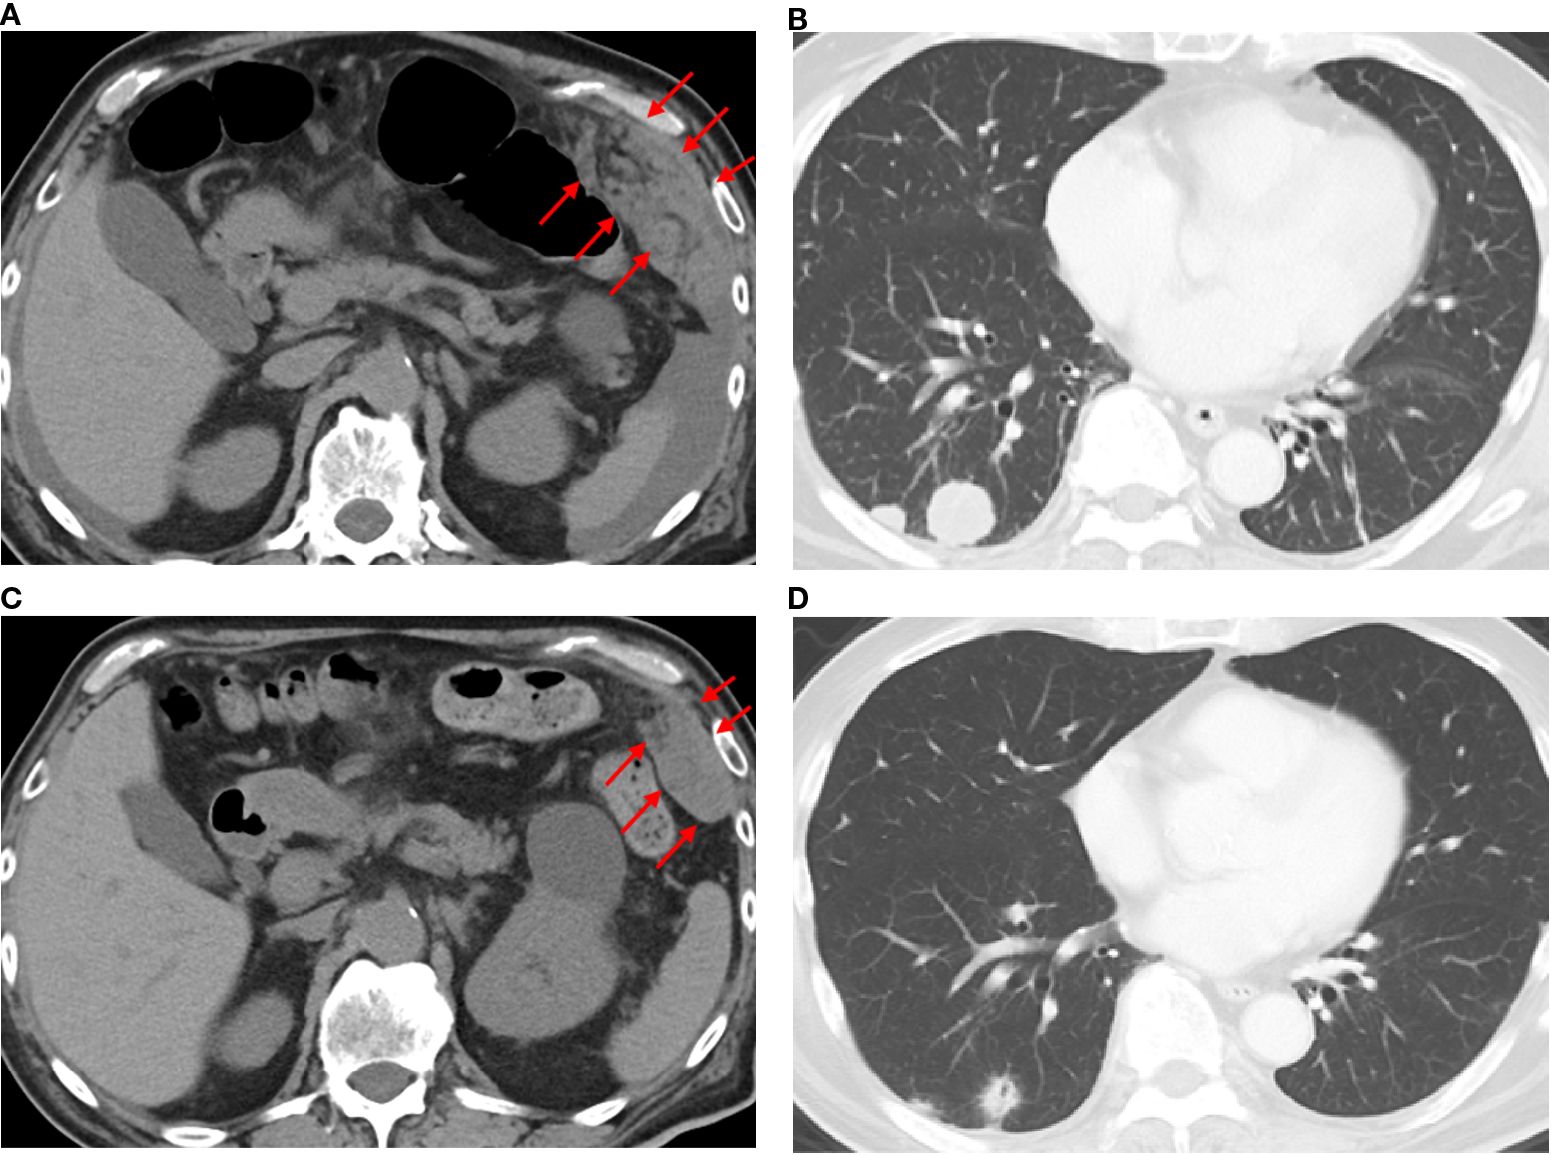

The final diagnosis was an adenocarcinoma arising in a Meckel’s diverticulum, classified as clinical Stage IV (pT3N2M1) based on the Union for International Cancer Control TNM (UICC TNM) Classification, 8th edition. This cancer diagnosis was discussed with a multidisciplinary cancer board, including a surgeon, an oncologist, and a gastroenterologist. Finally, distant metastasis was identified; therefore, chemotherapy was determined to be the optimal treatment. Additional immunohistochemical evaluations relevant to gastric cancer revealed that the tumor cells were Claudin 18.2 (CLDN18.2)-positive (Figure 3), HER2-negative, and mismatch repair (MMR)-proficient. Repeat CT at our institution revealed rapid tumor growth over a short period, with a Ki-67 labeling index of approximately 70% (Figures 2, 3), indicating high proliferative activity. Given the gastric-type histology and CLDN18.2 positivity, combination chemotherapy with zolbetuximab plus FOLFOX was started. After 2 months of treatment, a follow-up CT scan showed a marked reduction in the size of peritoneal dissemination and pulmonary metastasis, achieving a partial response based on the Response Evaluation Criteria in Solid Tumors (RECIST) criteria (Figure 4). Presently, the patient is 4 months into chemotherapy with a maintained response.

Figure 4

CT scans showing four panels. Panel A and C display abdominal cross-sections with red arrows indicating specific areas, likely highlighting areas of interest. Panel B and D show lung cross-sections within the chest cavity, displaying structures such as bronchi and pulmonary vessels, without specific annotations.

Figure 4. Computed tomography findings before and after the administration of zolbetuximab-based chemotherapy. CT images before treatment (a, b) and 2 months after zolbetuximab-based chemotherapy (c, d). Red arrows indicate peritoneal disseminated nodules.